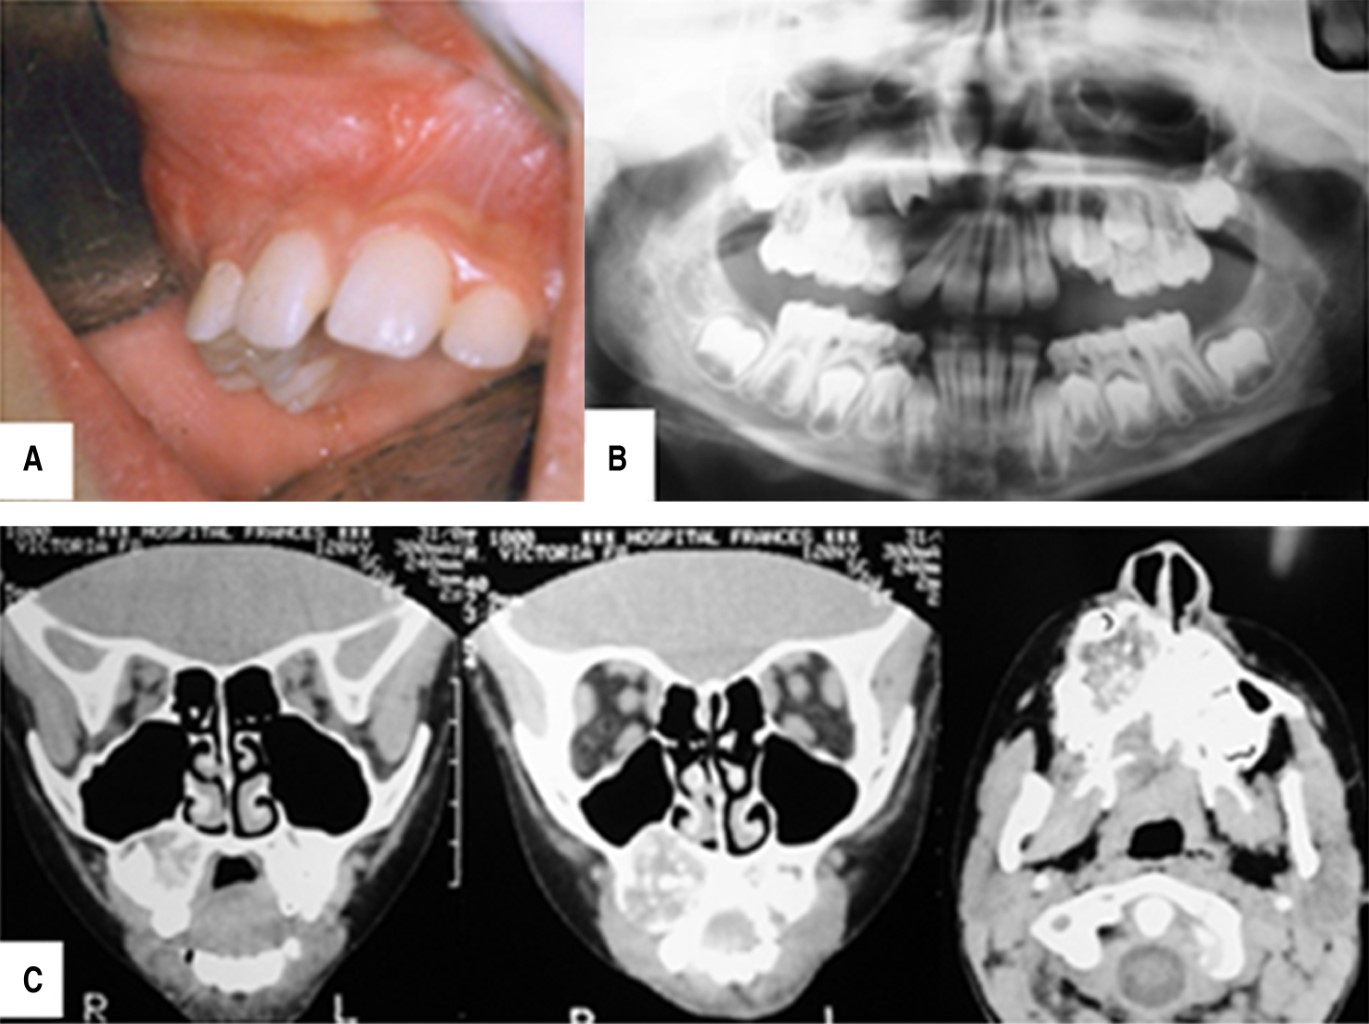

Figure 1